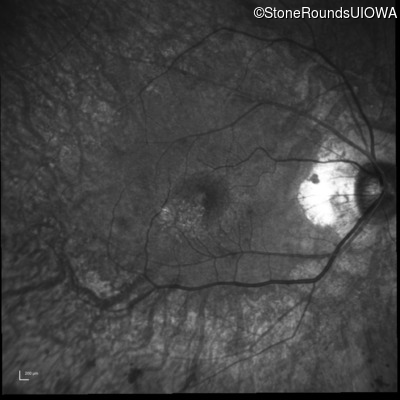

Infrared Fundus Photograph - Left - 20/20 -2

Exemplar